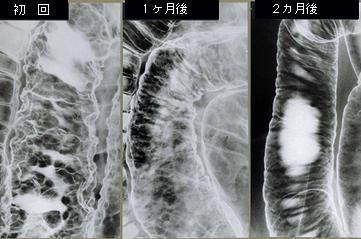

Pneumatosis cystoides intestinalis of the sigmoid colon demonstrating a reduction in size and number by high pressure oxygen therapy (no. 2)

Tumor-like lesions/Pneumatosis intestinalis

Location

Large intestine(Colon)/Sigmoid colon

Technique, Method

X-ray